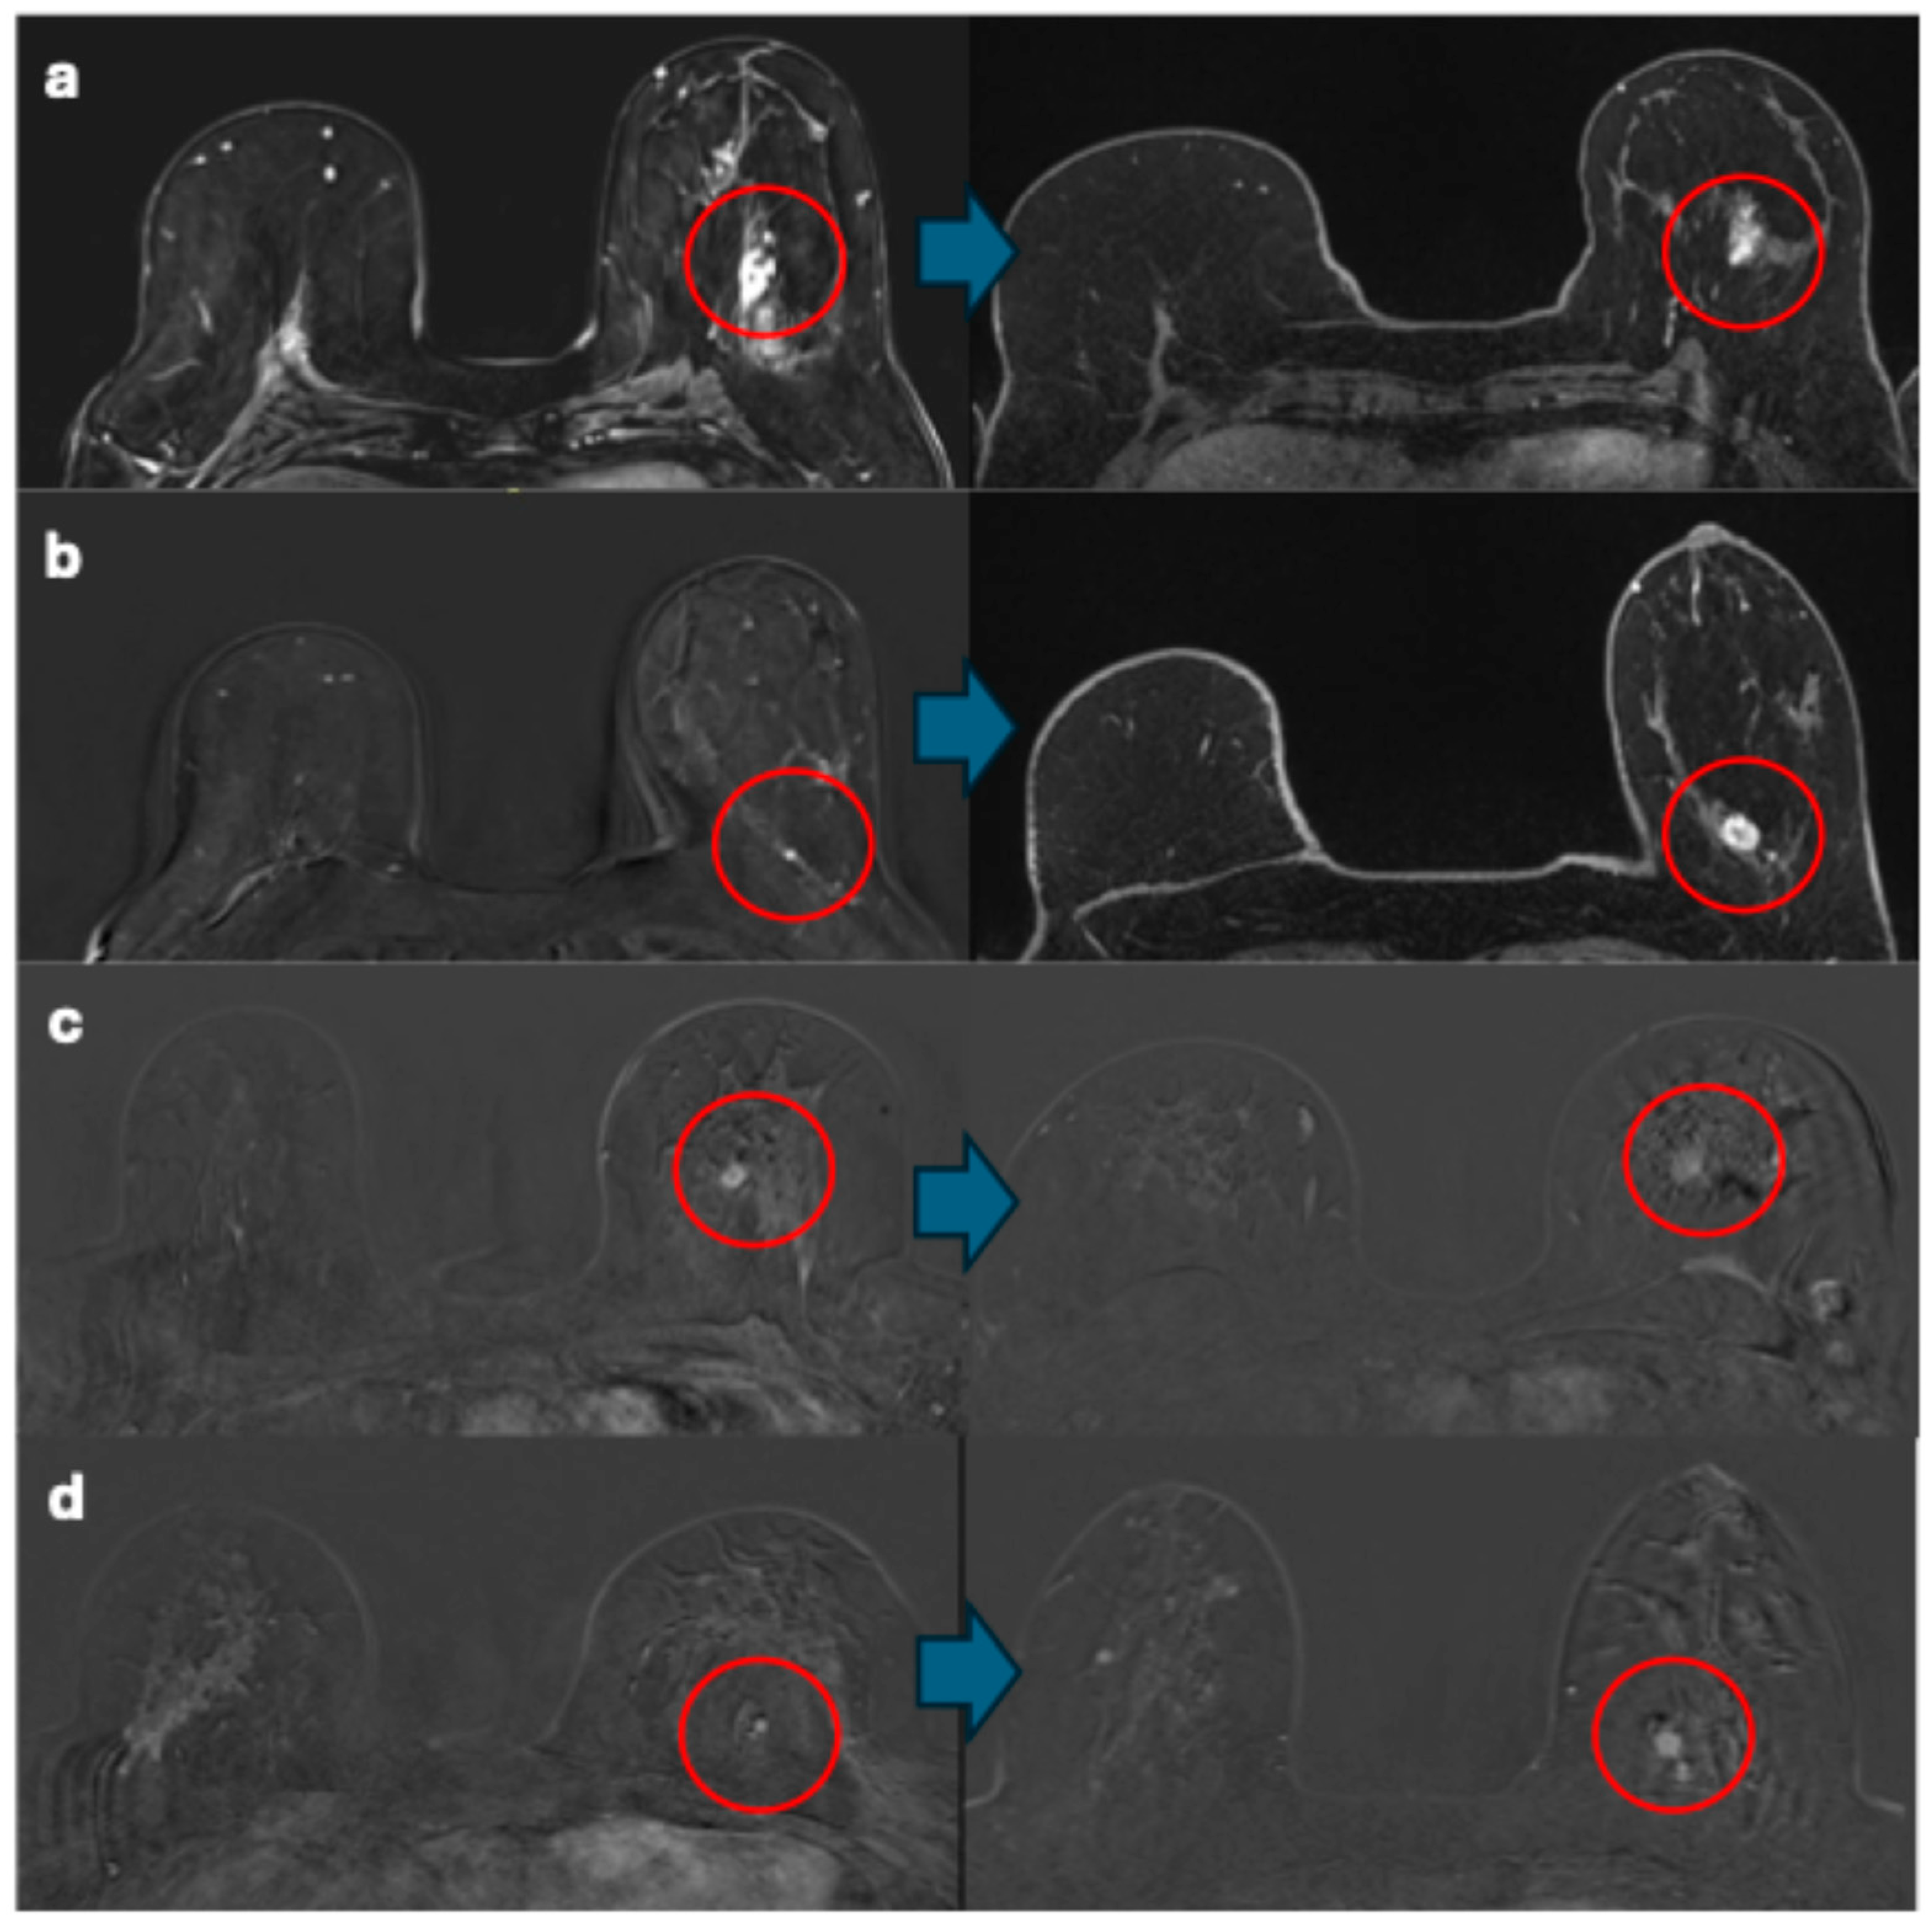

The remaining nine breast cancers were identified through surveillance (one in the prevalent round and eight in incident rounds) and described during the re-evaluation of the images. Of the eight breast cancers detected in incident rounds, four breast cancers were identified by both radiologists in both the baseline and detection MRI examinations. The median time between baseline and detection examinations for these breast cancers visible at baseline was 1.5 years (range, 1–2 years). In the comparison of baseline to detection MRIs, the lesions were visible but not necessarily deemed suspicious (Figure 5).

Figure 5.

(a) One breast cancer showed no change in size (30 mm), features (non-mass enhancement), or enhancement curves (type III) from baseline to detection. (b) One breast cancer showed changes in size, features, and enhancement curves from baseline (5 mm, focus, type I) to detection (18 mm, oval mass, type III). (c,d) Two breast cancers exhibited changes in features and enhancement curves from baseline (oval masses, type I) to detection (irregular masses, type III). Red circles indicate the breast cancers. Blue arrows connect the baseline images to the detection images.